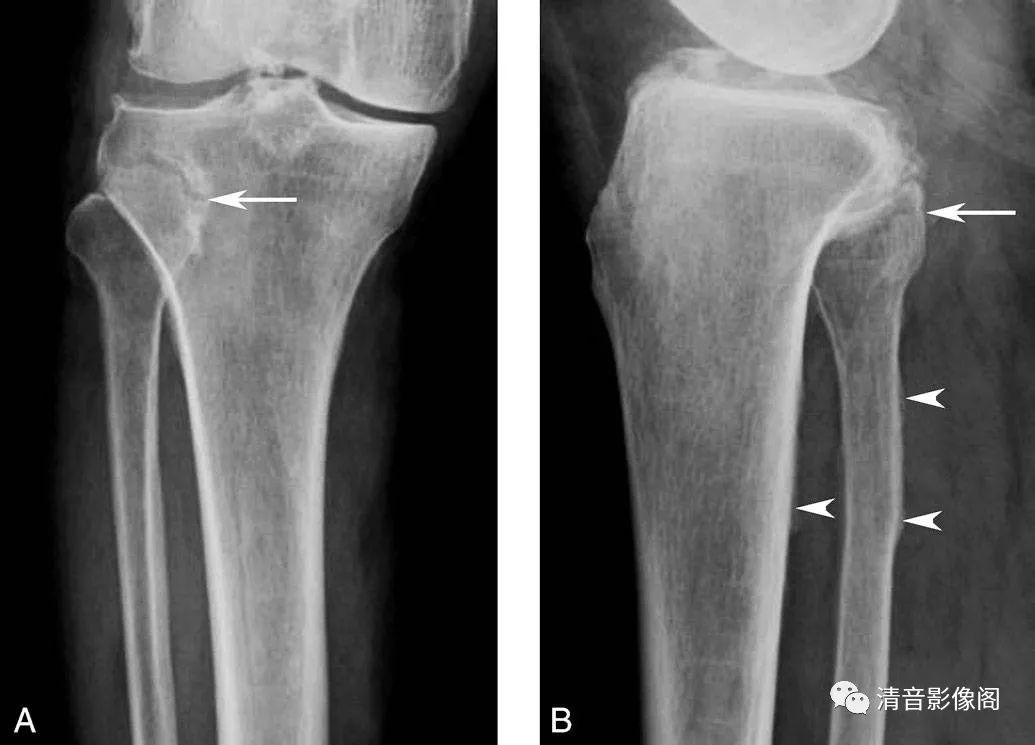

腓骨颈骨软骨瘤

A. 右膝关节X线正位;B. 右膝关节X线侧位。腓骨颈部可见异常局限性隆起(箭),皮、髓质均与腓骨相延续,远端见钙化,此皆为骨软骨瘤的特征性征象。